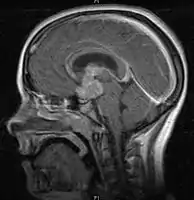

- Mainly located in midline structures, suprasellar region or pineal gland, also basal ganglia and hypothalamus

- Natural spread believed to be along subependymal lining of 3rd and 4th ventricles, leading to intraventricular relapse before spinal dissemination

- Pineal Gland Germinoma

- Suprasellar Germinoma